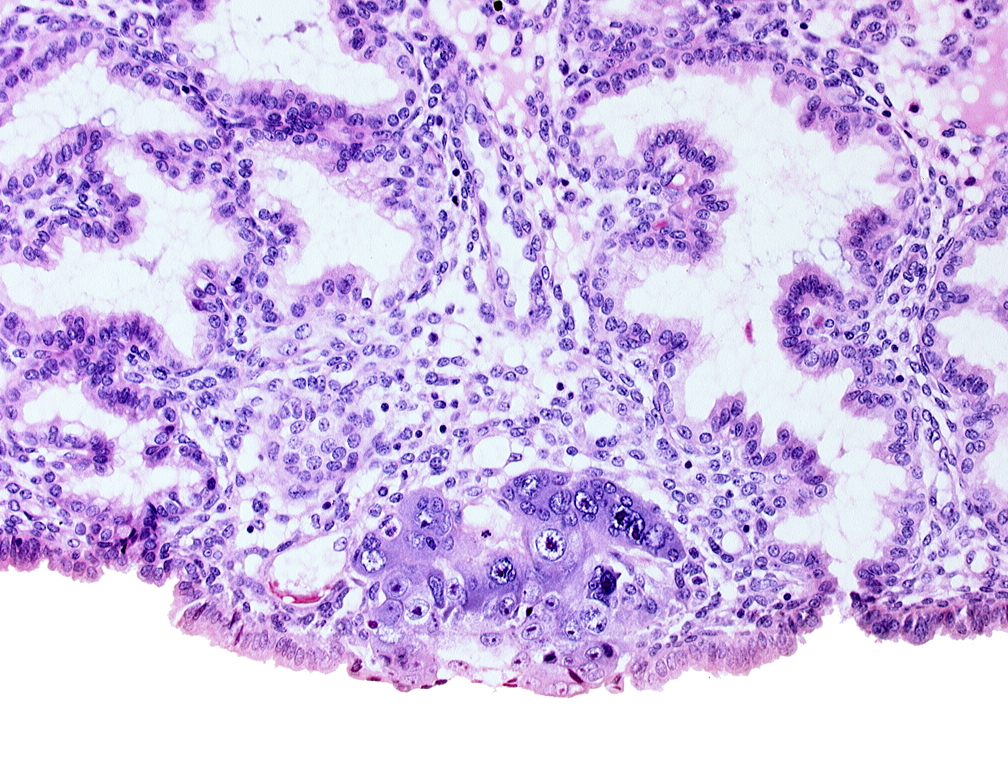

Carnegie Embryo #8155 | Location: 04-01-10

Keywords: blastocystic cavity (blastocoele), endometrial sinusoid, extra-embryonic mesoblast, membranous trophoblast at abembryonic pole, mouth of adjacent endometrial gland, syncytiotrophoblastic mass

Source: The Virtual Human Embryo.